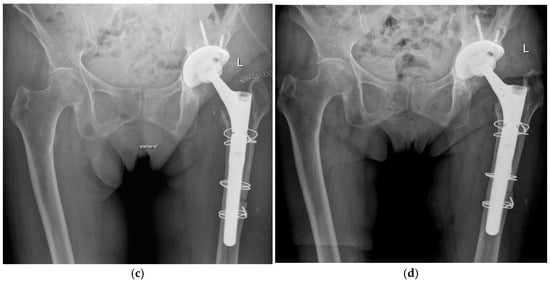

During the first-stage procedure, the infected implants were removed, and a cemented antibiotic-loaded spacer was implanted (104 times using an endofemoral approach and 182 times using a transfemoral approach) (Figure 1). The local antibiotic admixture was selected according to the antibiogram, as described previously [2,6]. The most frequently used antibiotics were gentamicin, clindamycin, and vancomycin, which were consistently applied in combination to optimize local bioavailability and improve elution characteristics. Radical debridement was performed, and a local antiseptic solution was applied. Additional intraoperative samples for microbiology and histology were obtained. Postoperatively, patients received a standardized antibiotic regimen consisting of 2 weeks of intravenous therapy followed by 4 weeks of oral antibiotics according to the antibiogram of the microorganisms.

Figure 1.

Radiographs of a two-stage procedure using a transfemoral approach performed on a 87-year-old women: (a) infected prosthesis with loosening of the cup and cemented stem; (b) temporary implanted spacer with cemented cup and cemented stem using a transfemoral approach; (c) reimplanted cementless prosthesis using the transfemoral approach; (d) one year follow-up of the reimplanted prosthesis with osseointegration of the components into the bone.

At the time of reimplantation, the spacer was removed, followed by thorough debridement, application of a local antiseptic solution, and reimplantation of a new prosthesis (Figure 1). Again, patients received 2 weeks of intravenous antibiotics followed by 4 weeks of oral therapy, according to the susceptibility of microorganisms.